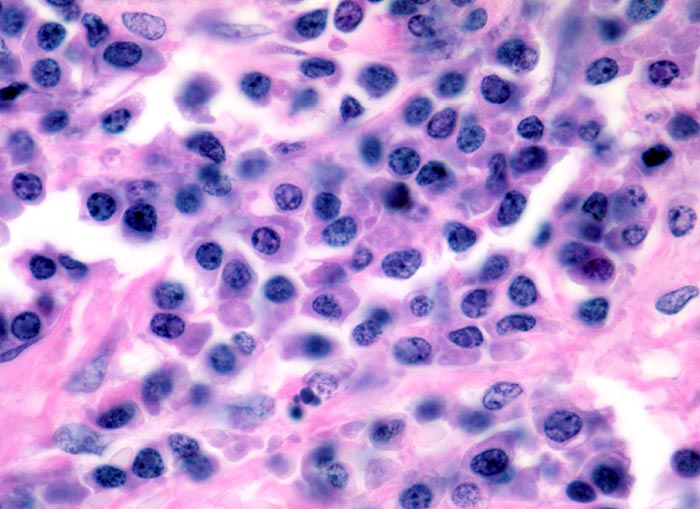

In dieser Giemsa-Färbung sind die Plasmazellen gut erkennbar. Die Plasmazellen sind polymorph, vereinzelt mehrkernig. Exzentrisch im Zytoplasma lokalisierte vergrösserte Radspeichenkerne . Reichlich violettes Zytoplasma mit paranukleärer Aufhellung. Zellkerne teils mit vergrössertem Nukleolus.